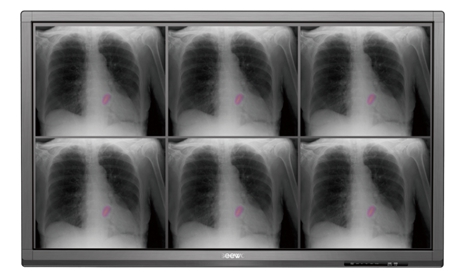

希沃交互智能平板的醫療機型,為醫療會診提供了一個嶄新的平臺。其采用了IPS液晶屏,在清晰度、色彩準確性、屏幕穩定性和視角廣度上都有優良表現。其4K*2K的高清顯示分辨率,10位灰階色的超高清顯示能力,更符合DICOM顯示曲線,使希沃醫療機型可全真實還原醫療影像,展現不刺眼的超細膩顯示效果。同時,其超廣可視角度可達178°,即使站在平板兩邊或前側方也能觀看到無色差顯示效果,進一步確保了醫療評估結果的精確性。

(希沃醫療機型可清晰還原醫學影像)

搭配希沃針對醫療顯示設計的軟件SeewoMedicalDicomViewer(SMDV),形成醫療顯示解決方案,可幫助醫生查看并分析醫學領域的CT,核磁共振等圖像,輔助診斷。該方案提供了智能測量工具,可以讓醫生們隨心所欲“指哪查哪”。通過在屏幕上滑動,用戶還可以調整圖像的窗值,輕松放大病灶,不遺漏任何細節。